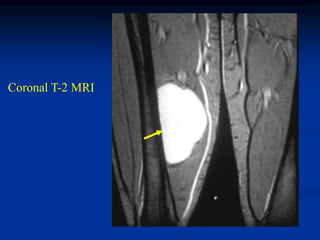

Case #1202

80 year male with

pleomorphic liposarcoma

Sagittal T-1 MRI

Sagittal T-2 MRI

Case #1202 80 yearmale with pleomorphic liposarcoma Sagittal T-1 MRI

• 255.